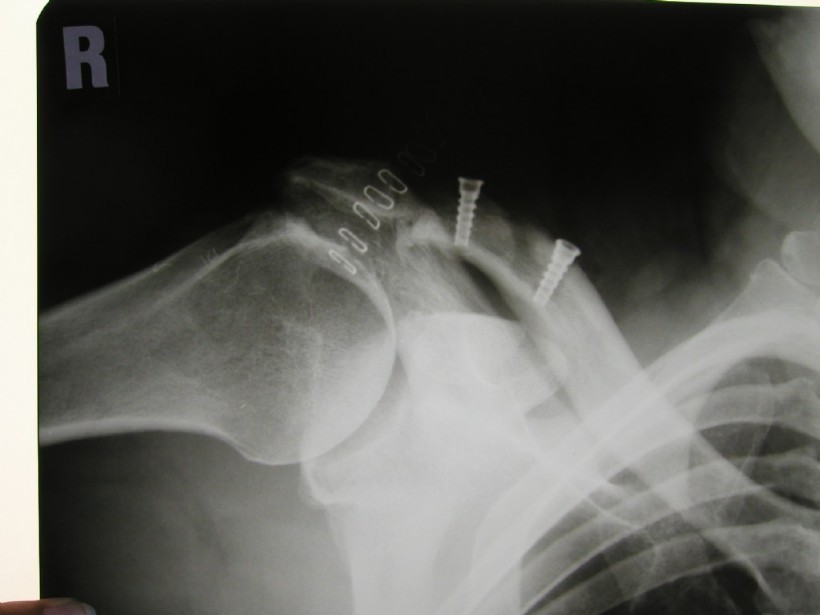

If the glenoid is too small, too low or inclined too far forward, or even broken at the front, the arthroscopic operation can not be performed.

In an open surgery (incision in the axilla extension, about 10 cm long) each present defect will be removed. Thus, in case of a too flat or too small glenoid, a bone graft from the own iliac crest is used to enlarge the glenoid.

The front edge of the socket is enlarged by a screwed bone graft.